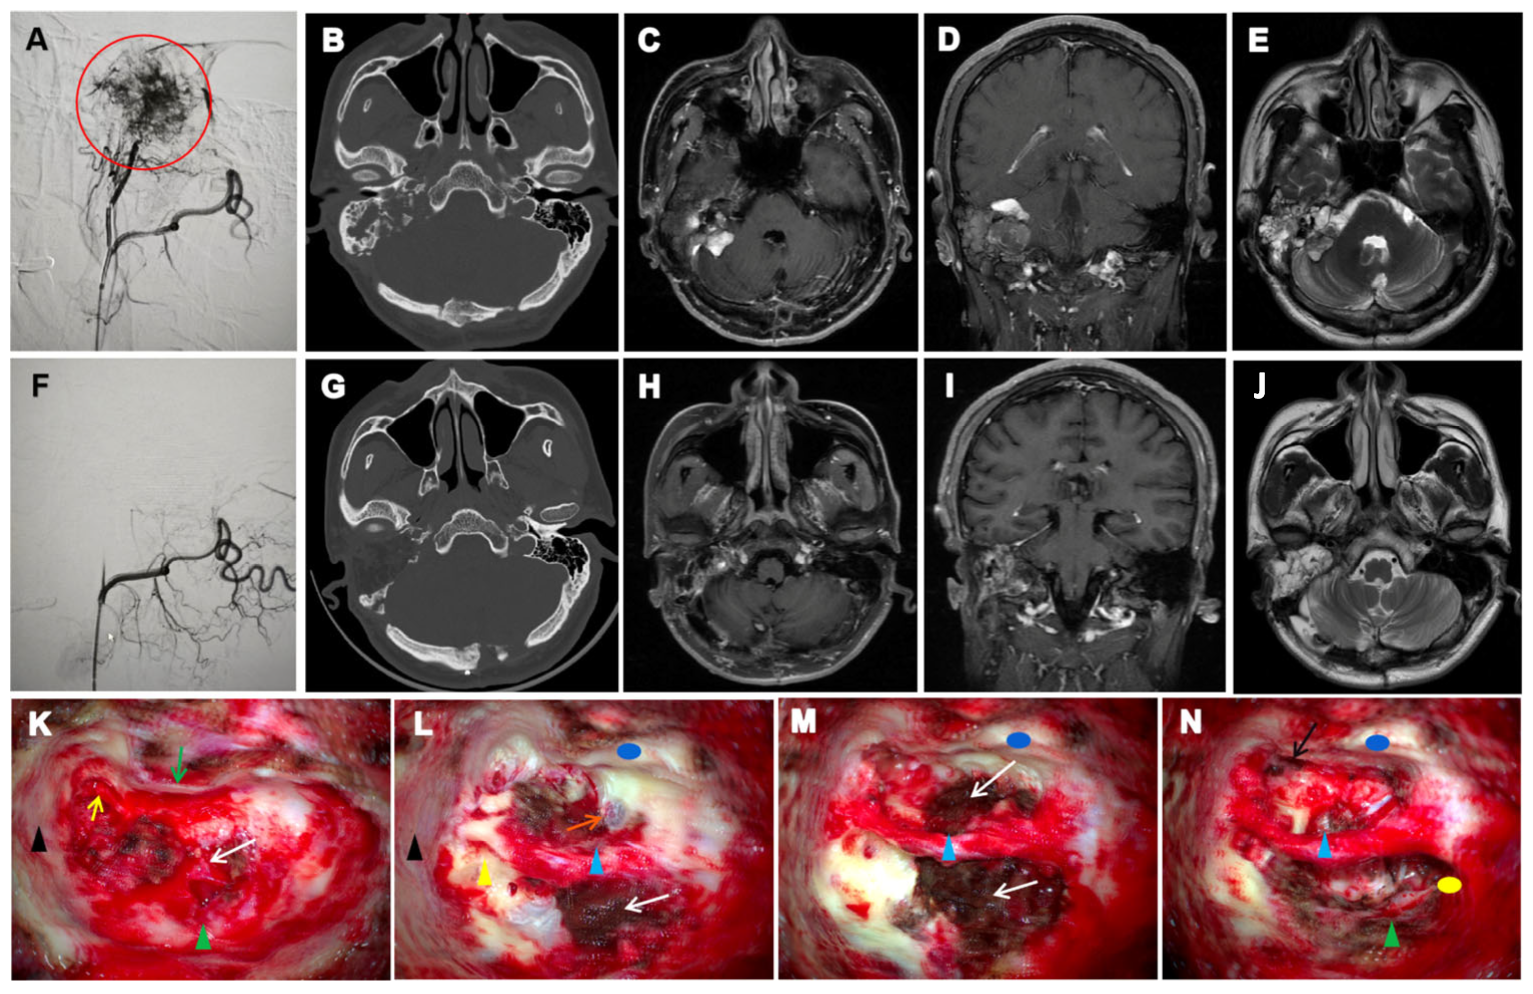

| HRCT | Assess bony erosion, tumor boundaries, and preoperative planning | ipsilateral temporal bone “moth-eaten” or honeycomb-like osteolytic destruction with crest-like/granular calcifications and residual bone formation | CT localization typically revealed tumour centres in the vestibular aqueduct operculum region, with early-stage lesions showing periaqueductal osteolysis and preserved surrounding architecture that facilitated origin identification. In advanced cases, the jugular foramen or subdural extension often obscured primary site determination. |

| MRI | Early screening, Lesion localization and classification, tumor relationship with the inner ear, brainstem, and cranial nerves, postoperative follow-up and long-term surveillance | hyperintense peripheral tumour margins and flow voids on T1-weighted imaging; and heterogeneous signal intensity on T2-weighted imaging. | Superior soft tissue contrast allows early detection of subclinical lesions, precise delineation of tumor extent, and assessment of involvement of critical neurovascular structures. Essential for surgical planning and long-term surveillance, especially in bilateral or recurrent VHL-associated cases. |

| DSA | Assess vascular supply and guide preoperative embolization | Tumor blush from external carotid artery branches; occasionally supplied by internal carotid or vertebral artery branches | Defines feeding arteries; essential for embolization planning and minimizing intraoperative bleeding risk |